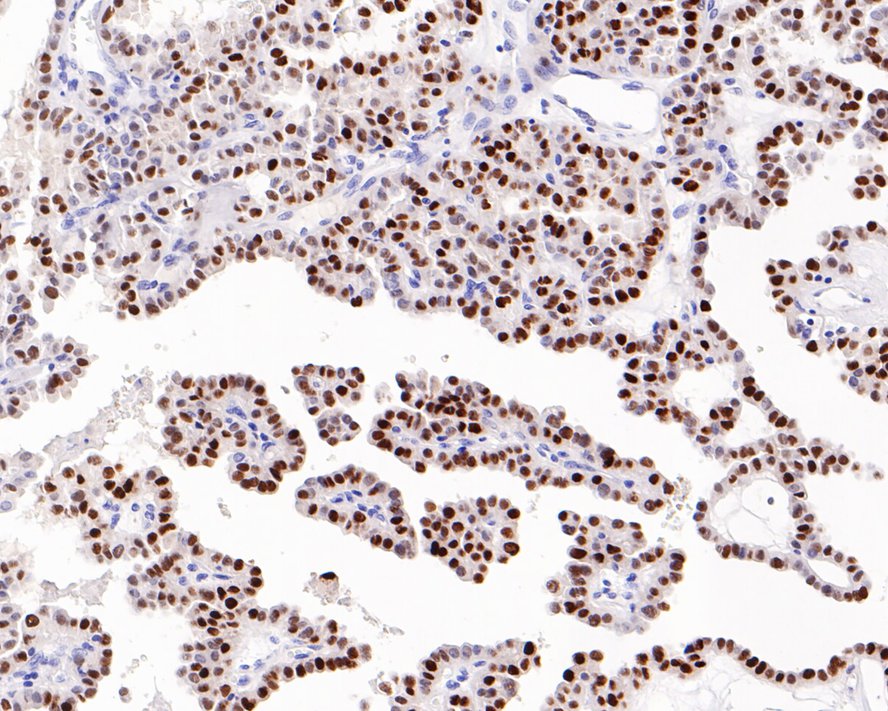

Catalog# HA601018

p21 Mouse Monoclonal Antibody [A8C11]

IHC-P

Human